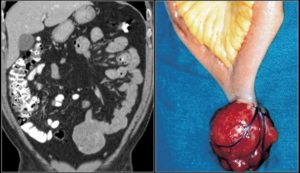

С помощью лапароскопии можно установить эндогастральную саркому желудка, то есть опухоль, которая поражает переднюю стенку желудка.

Использование эндоскопа в диагностике – самый эффективный метод. Именно лапароскопия позволяет определить опухоль желудка в самых труднодоступных местах. Поэтому врачи прибегают к эндоскопической операции.

Эндоскопия

Метод считается одним из наиболее эффективных. Как правило, его обычно назначают перед операцией.